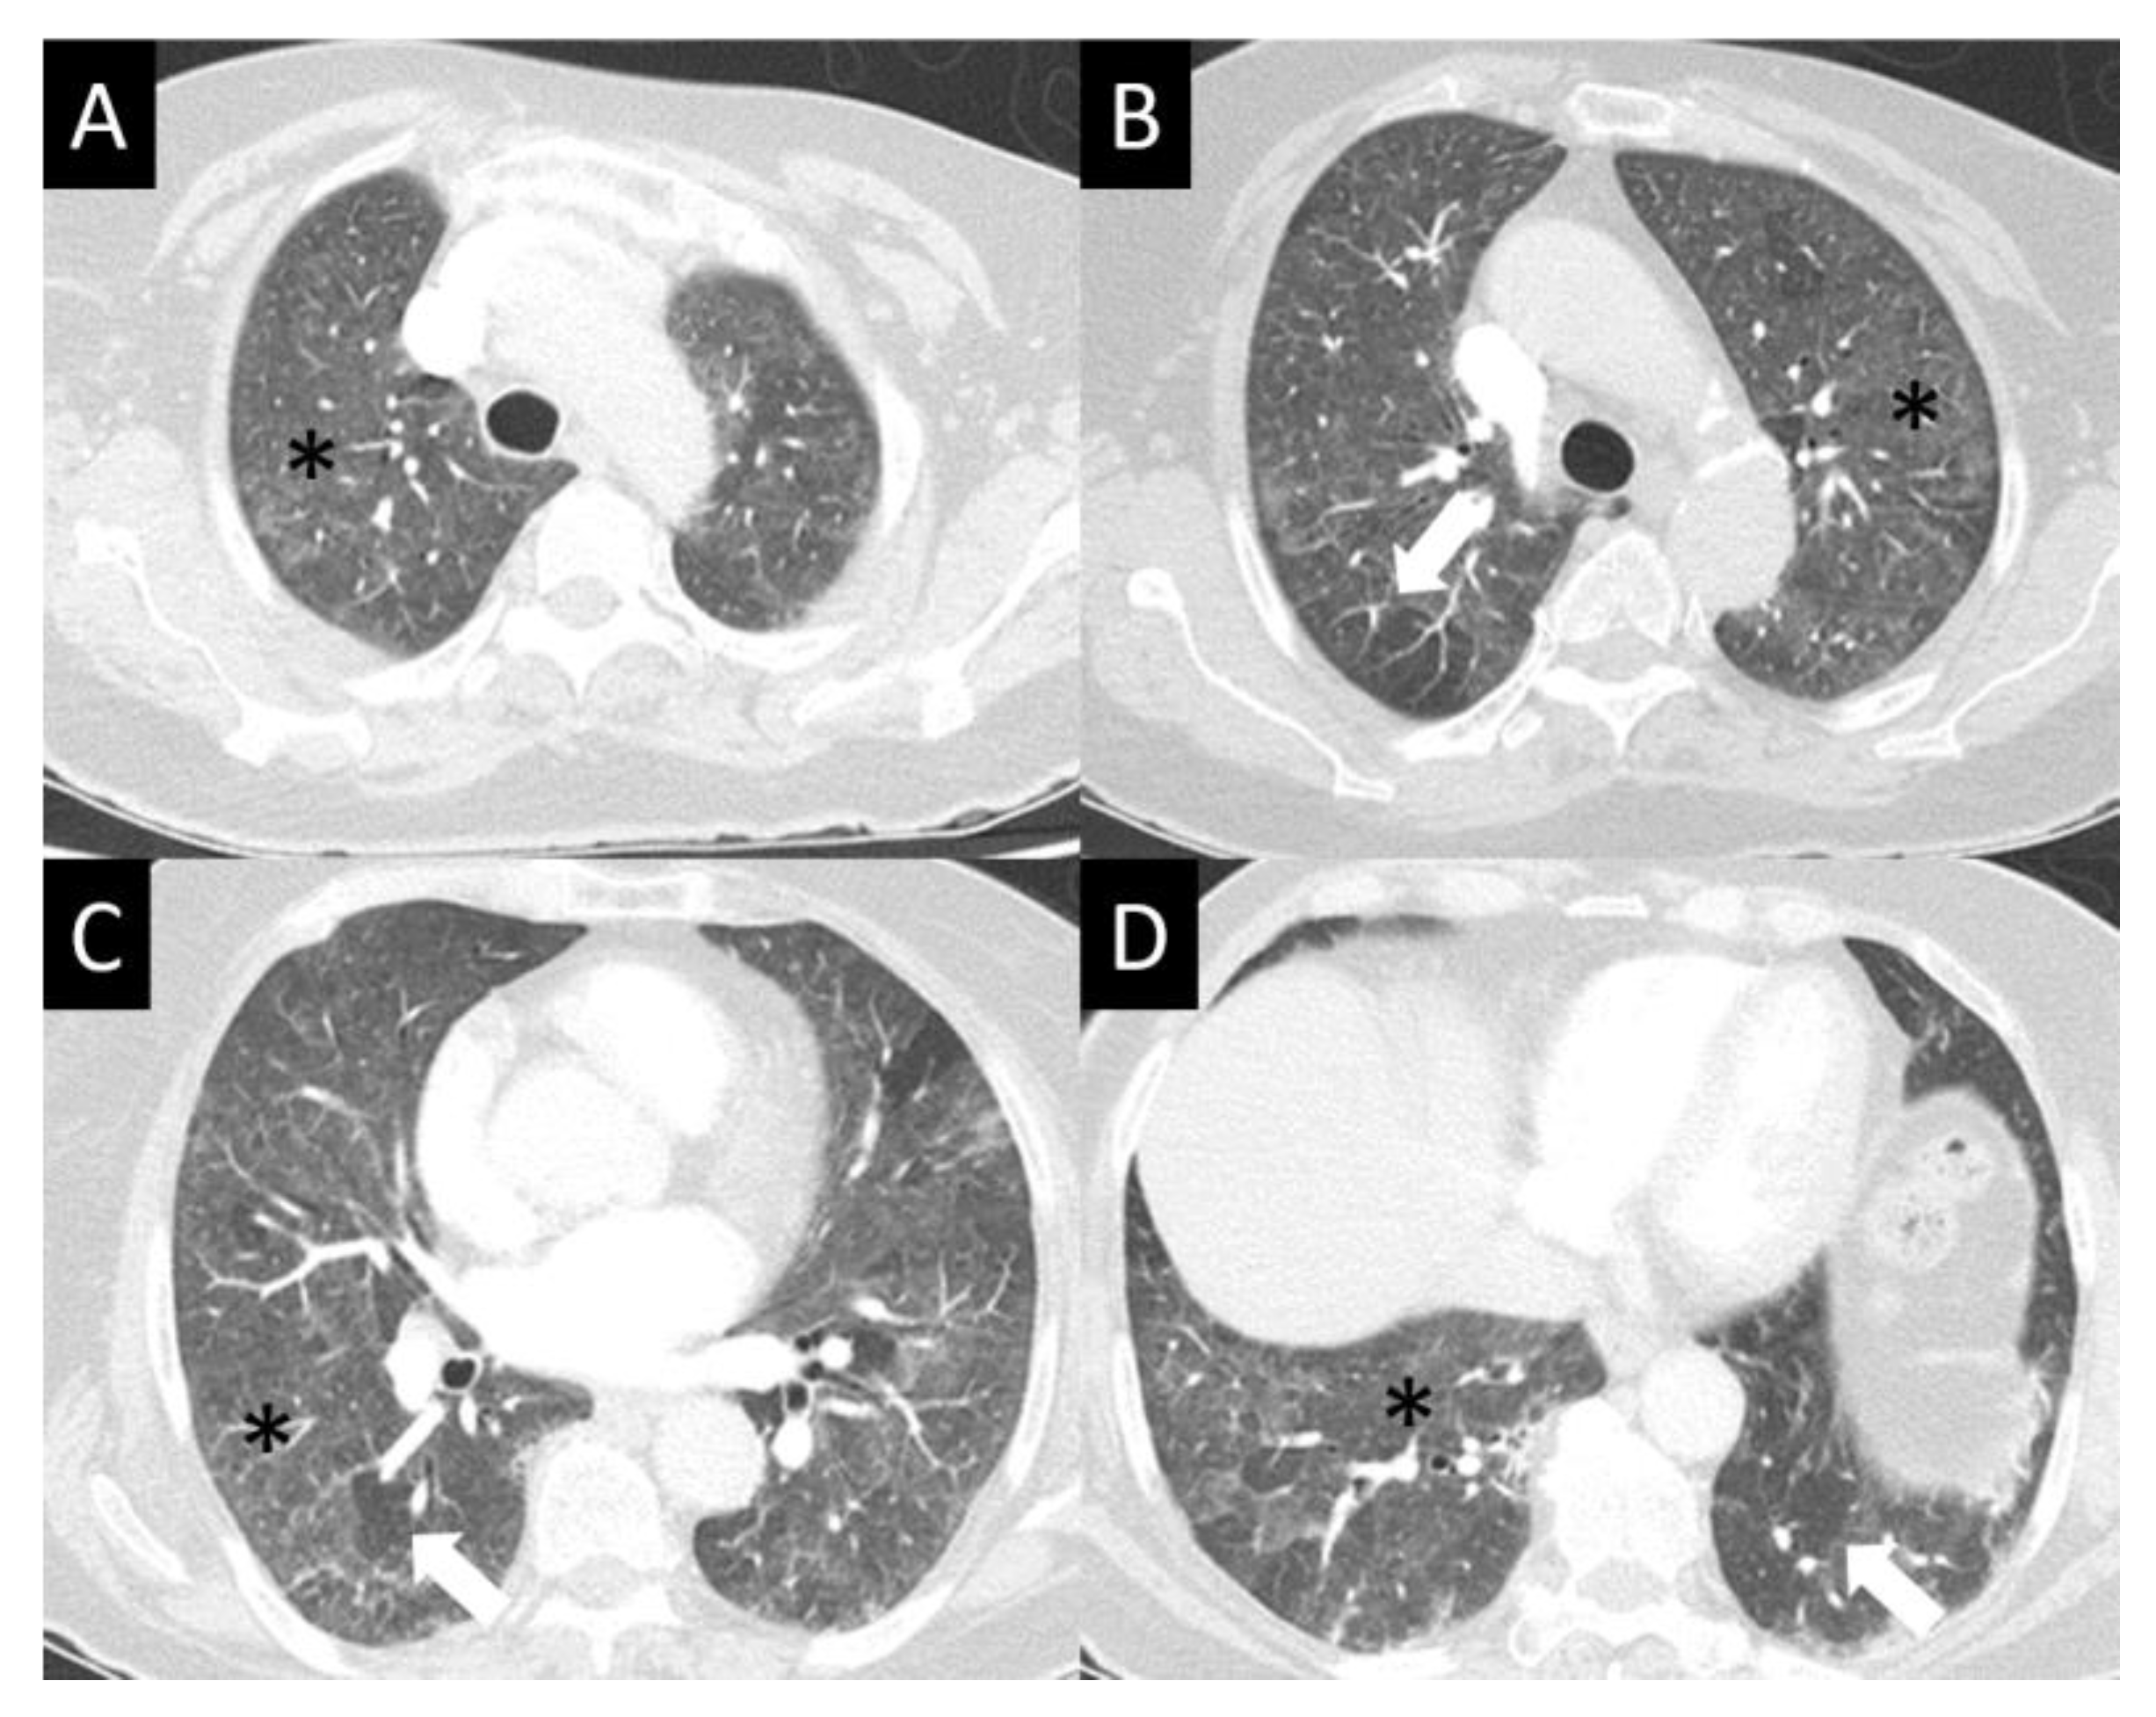

DAD is the most aggressive presentation and is usually present in grade 4 DI-ILD. Features of DAD on CT include ground glass opacities (GGOs) with associated areas of consolidative opacities (Figure 3). OP is characterized by multifocal areas of GGO and peripheral consolidation. Reversed halo/atoll signs may also be seen (Figure 4). NSIP is characterized by GGO, which tends to be basal with peripheral reticular opacities (Figure 5). Features of HP on CT include diffuse GGO, ill-defined centrilobular nodules, mosaic attenuation on inspiratory images, and air trapping on expiratory CT images (Figure 6).

Figure 6.

Hypersensitivity pneumonitis (HP) (A–D). HP often presents in its nonfibrotic form—seen here as subtle but diffuse ground glass opacity (GGO, asterisks), sometimes with an aspect of centrilobular nodularity. While GGO is nonspecific, mosaic lung attenuation with patchy spared lobules (arrows) is typical of the air trapping seen in HP.